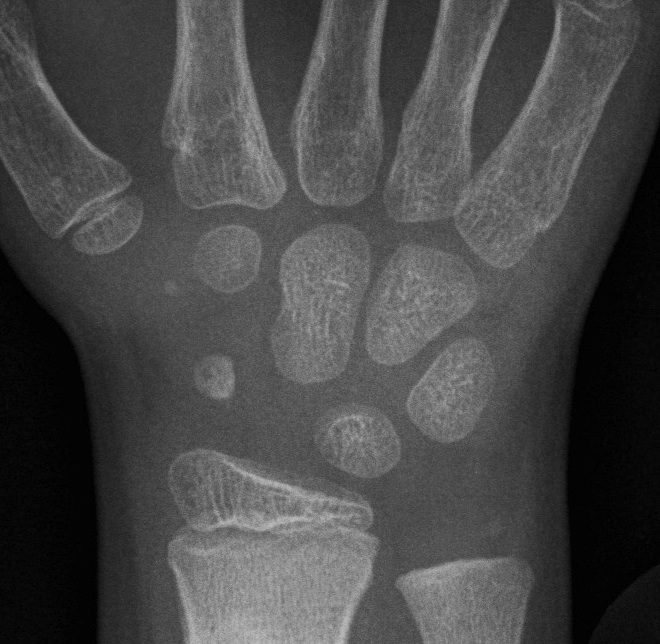

Skeletal Age

1. Greulich- Pyle Atlas

Xray Left hand (non dominant)

- correlated with Green- Anderson table LL

- less accurate < 6

- improved accuracy by focusing on hand bones rather than carpal bones

2. Tanner- Whitehouse Atlas

- more refined

- 20 landmarks graded L Hand

- more accurate

- can't use as not correlated with LL